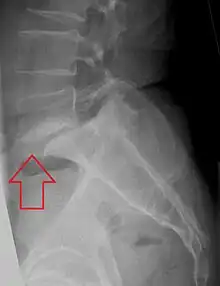

X-ray of measurement of spondylolisthesis at the lumbosacral joint, being 25% in this example

Classification by degree of the slippage, as measured as percentage of the width of the vertebral body:[14] Grade I spondylolisthesis accounts for approximately 75% of all cases.[6]

- Grade I: 0–25%

- Grade II: 25–50%

- Grade III: 50–75%

- Grade IV: 75–100%

- Grade V: greater than 100%